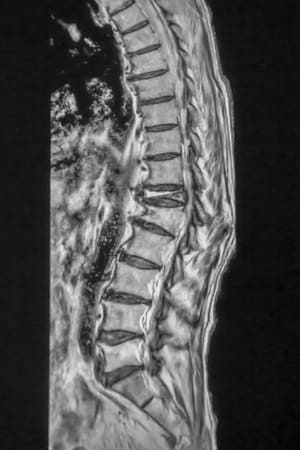

背中が丸くなる原因としてまず挙げられるのが、骨粗鬆症による「圧迫骨折」です。

骨粗鬆症は加齢によって骨の密度が低下し、骨がスカスカになってしまう状態で、特に女性は閉経後にホルモンバランスが変わる影響で、骨が弱くなりやすくなってしまいます。

骨粗鬆症になると、くしゃみや立ち上がりなどの日常動作でも背骨がつぶれるように骨折してしまうことがあります。これが圧迫骨折です。

圧迫骨折による背骨の潰れは、徐々に背中を前に曲げてしまうのです。